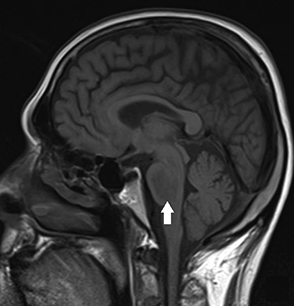

Brain magnetic resonance imaging of a patient with central pontine myelinolysis showing hypointensity within the basis pontis

BMJ Case Reports 2013; doi:10.1136/bcr-2013-009970